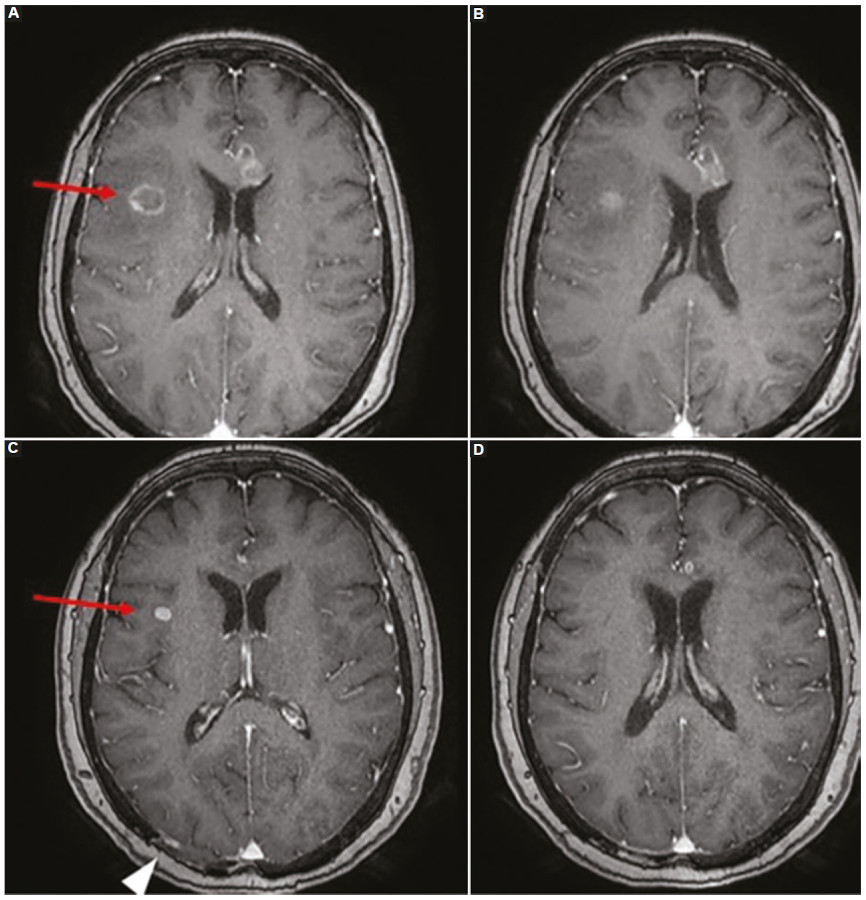

Las lesiones por SLPT del parénquima encefálico suelen ser masas corticales y subcorticales intraaxiales múltiples, con hemorragia, necrosis y edema perilesional, en general ubicadas en las estructuras supratentoriales más profundas, los ganglios basales, el tálamo y la región periventricular. Sin embargo, también pueden verse en el cerebelo y tronco encefálico48. Las lesiones tienden a infiltrar los tractos de sustancia blanca, incluido el cuerpo calloso y la cápsula interna. Las características de neuroimagen del SLPT son similares a las que se observan en personas inmunodeprimidas con linfoma primario del SNC11,48. En la TC, las lesiones parenquimatosas son isodensas-hiperdensas en relación con la corteza debido a su alta celularidad, característica que condiciona hipointensidad en secuencias ponderadas en T2 en la RM. Asimismo, con respecto a las demás secuencias de RM, las lesiones del SLPT se visualizan hipointensas o isointensas en secuencias ponderadas en T1, con áreas hiperintensas ocasionales que se deben a hemorragia intratumoral, con edema vasogénico peritumoral moderado. Ante la administración de contraste endovenoso se observa un patrón de realce en anillo similar al de un absceso cerebral en el 87% de los casos, o menos frecuentemente, con realce homogéneo, acompañado de edema vasogénico perilesional48) (Fig. 9).

Uno de los hallazgos característicos del SLPT del SNC es la marcada restricción en secuencias de difusión de la periferia de la lesión debido a la hipercelularidad, que corresponde a las áreas de realce periférico luego de la administración de gadolinio. Contrariamente a la apariencia de las lesiones de SLPT, los abscesos piógenos y, con menos frecuencia, los abscesos fúngicos pueden mostrar una difusión central restringida, ambos diagnósticos diferenciales del SLPT del SNC848.

La frecuencia de afectación leptomeníngea puede subestimarse porque es difícil de diagnosticar en la RM. Puede aparecer como realce leptomeníngeo, subependimario o dural48.